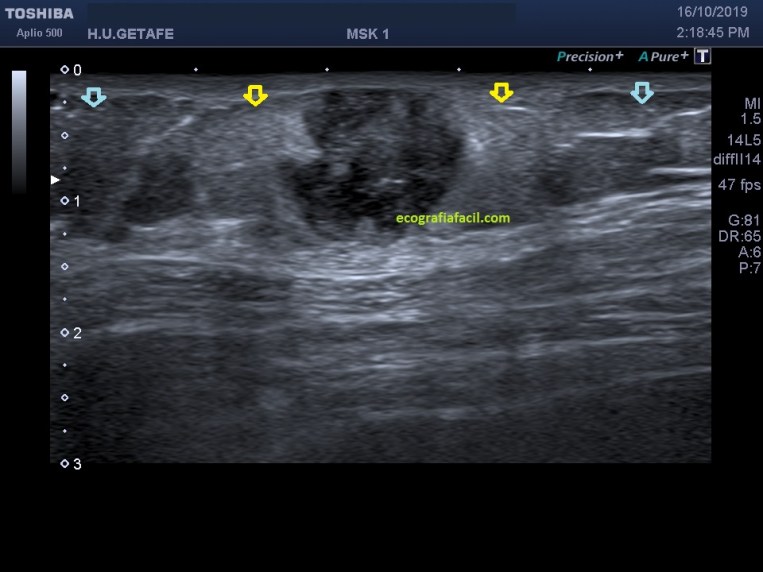

Lo primero que tenemos que tener claro es la anatomía. En la imagen «anatomía» te marco todo estratificado para que te des cuenta del nivel en el que se presenta la lesión que debemos estudiar, es importante que te fijes en la piel, si está respetada o no.

Después es muy importante que te fijes en el TCS, que es vital porque es donde se encuentra la lesión. Es una lesión que está dañando o infiltrando el TCS circundante, que está hiperecogénico en la imagen 4 y 5 puedes apreciar perfectamente las diferentes ecogenicidades semiológicas. La flecha amarilla marca la zona infiltrada del TCS y en azul celeste la ecoarquitectura preservada.

La LOE (lesión ocupante de espacio) es hipoecogénica, heterogénea, sólida, con bordes definidos, pero agrestes, aunque respeta tanto la piel como la fascia.

No es un absceso, porque es sólido, por eso el diagnóstico principal fue implante metastásico subcutáneo.